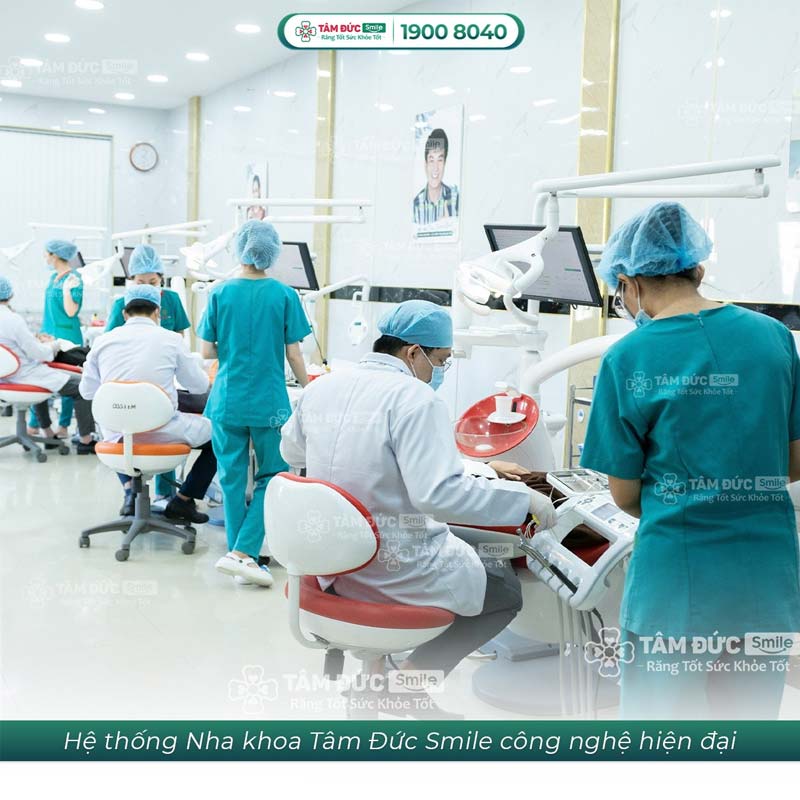

3. Nhổ răng khôn an toàn, hiệu quả tại nha khoa Tâm Đức Smile

Nha khoa Tâm Đức Smile là một trong những địa chỉ nha khoa uy tín, cung cấp dịch vụ nhổ răng khôn an toàn. Tâm Đức Smile áp dụng công nghệ nhổ răng khôn hiện đại, giúp quá trình tiểu phẫu diễn ra nhanh chóng, nhẹ nhàng, hạn chế xâm lấn, mau lành thương.

Quy trình nhổ răng khôn tại nha khoa Tâm Đức Smile được thực hiện theo tiêu chuẩn của Bộ Y tế, đảm bảo an toàn tuyệt đối. Các bác sĩ tại nha khoa đều là những chuyên gia giàu kinh nghiệm, được đào tạo bài bản với thao tác nhổ răng nhẹ nhàng.